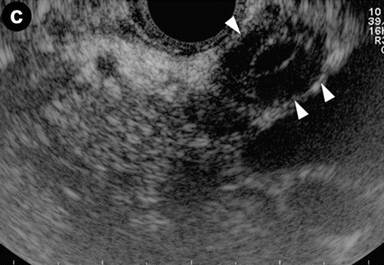

Patient#7: Focal form of autoimmune pancreatitis, with common bile duct involvement.

A 43-year-old woman with recurrent abdominal pain, jaundice and elevated levels of IgG4 (264 mg/dL). Transabdominal US and CT showed an enlarged pancreatic head, slightly dilated intra-hepatic bile ducts with a stricture of the intra-pancreatic common bile duct, and a distal focal stricture of the main pancreatic duct. Intraductal sonography performed during ERC revealed that the common bile duct stenosis was due to bile duct wall thickening (arrows) (Image 7), with a "sandwich-pattern".

|

Image 7 |